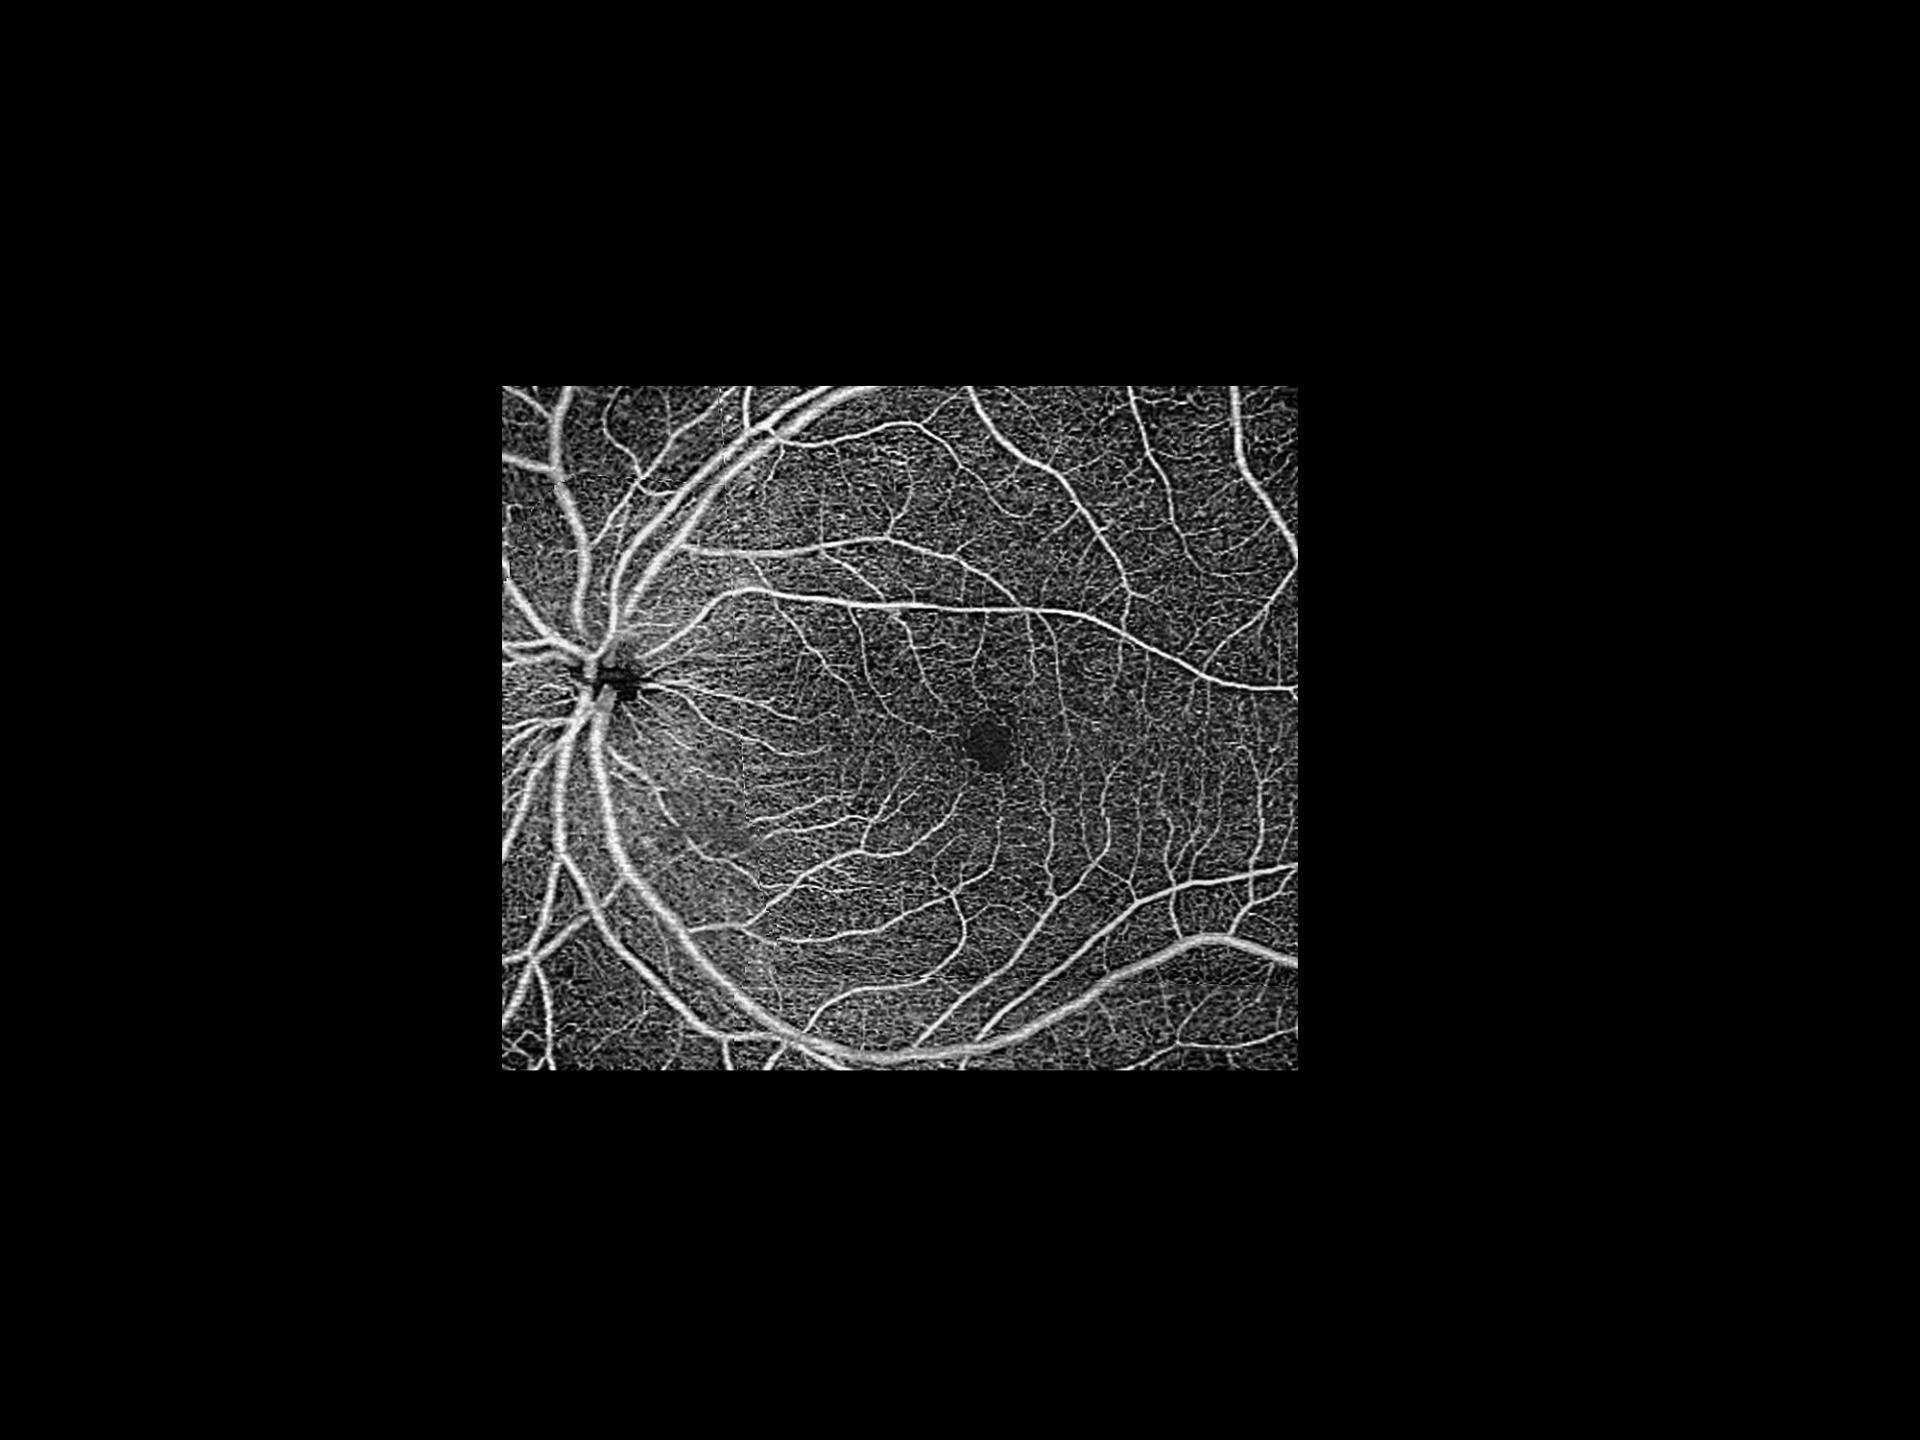

• AngioPlex for ONH of a normal eye

AngioPlex for ONH of a normal eye showing the blood vessels at the lamina cribrosa level.